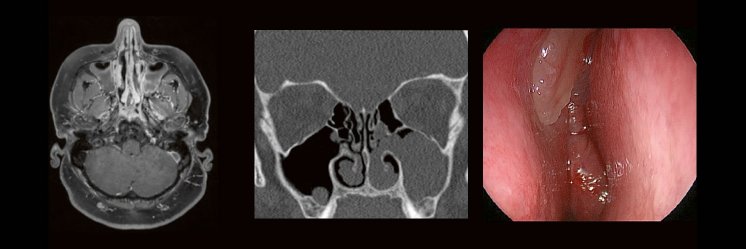

HNO & Radiologie: gemeinsam durch die NNH – ein Joint Venture

Die bildgebende HNO-Diagnostik macht es Anfängern nicht leicht. Die Anatomie ist komplex und weniger intuitiv als in anderen Körperregionen.

Normvarianten erschweren insbesondere in den Nasennebenhöhlen den Lernprozess. Sobald pathophysiologische Zusammenhänge verstanden und wichtige klinische Aspekte verinnerlicht wurden, gelingt es einen praxistauglichen, belastbaren Befund zu erstellen.

Gemeinsam mit einem HNO-Chirurgen werfen wir einen Blick IN die NNH – mal in grau, mal in Farbe. Denn alles fällt leichter, sobald man verstanden hat, warum man es tut.